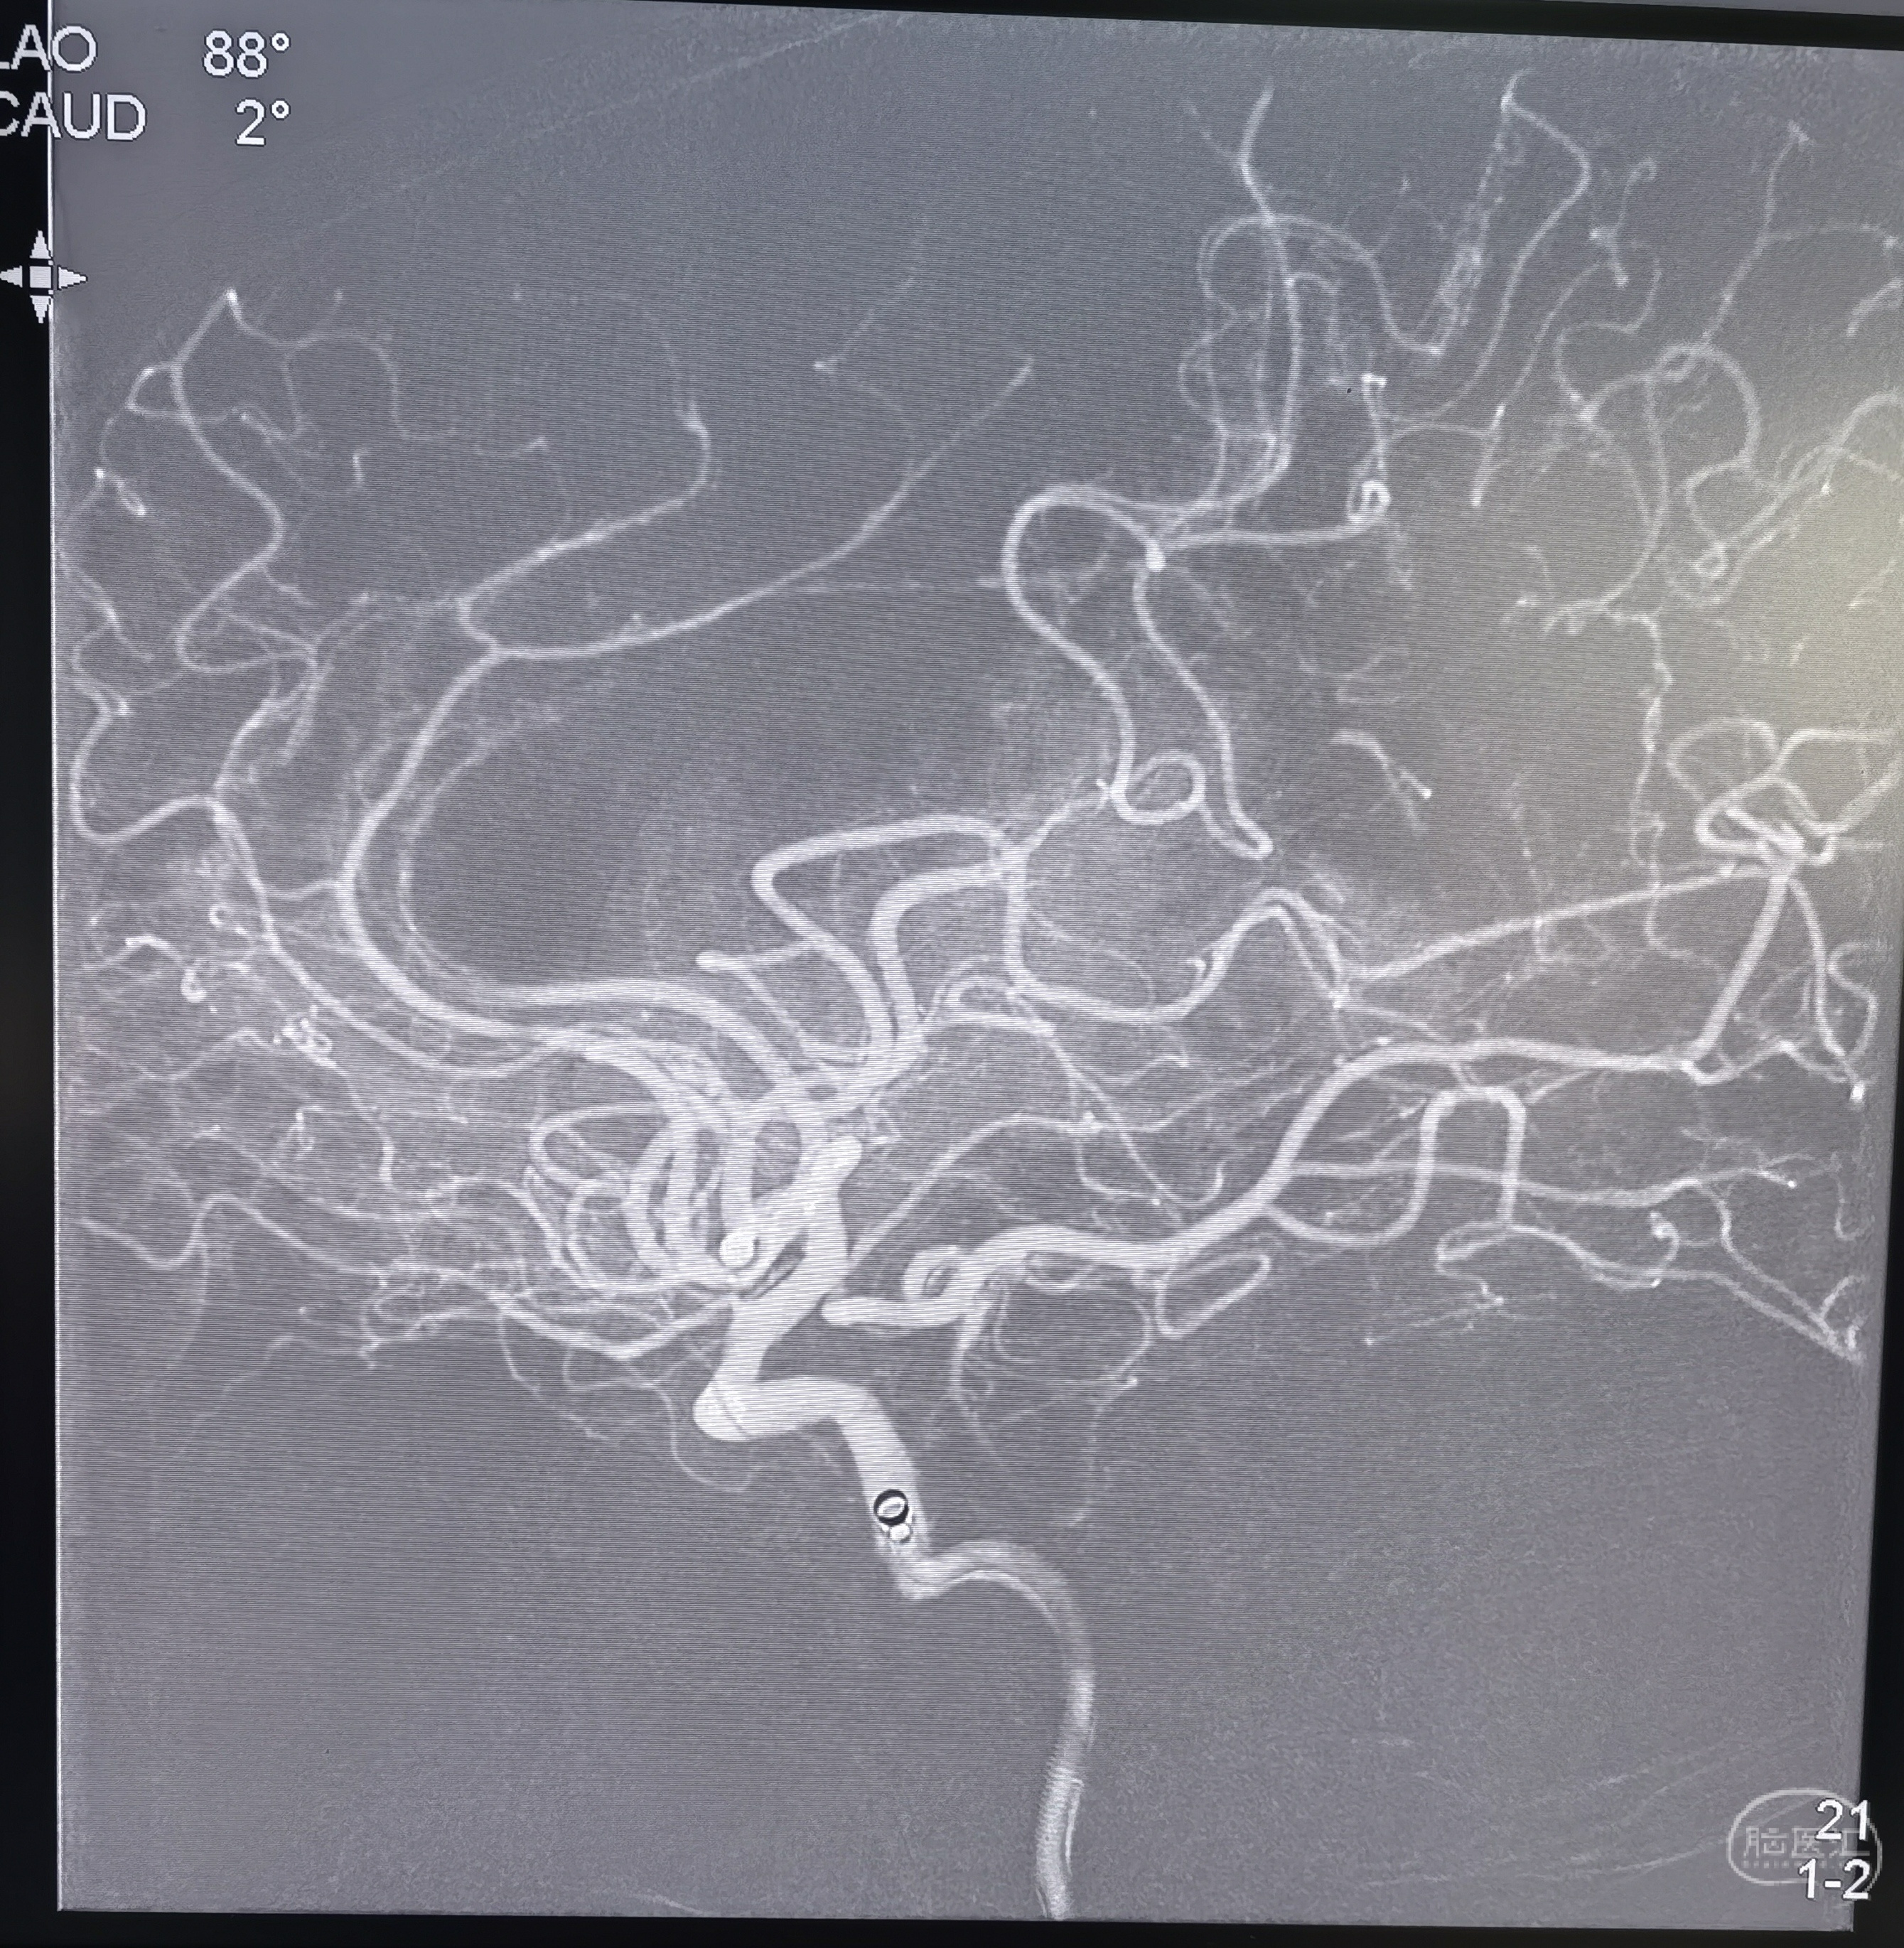

通过颈内动脉闭塞段后侧位造影

抽取血栓